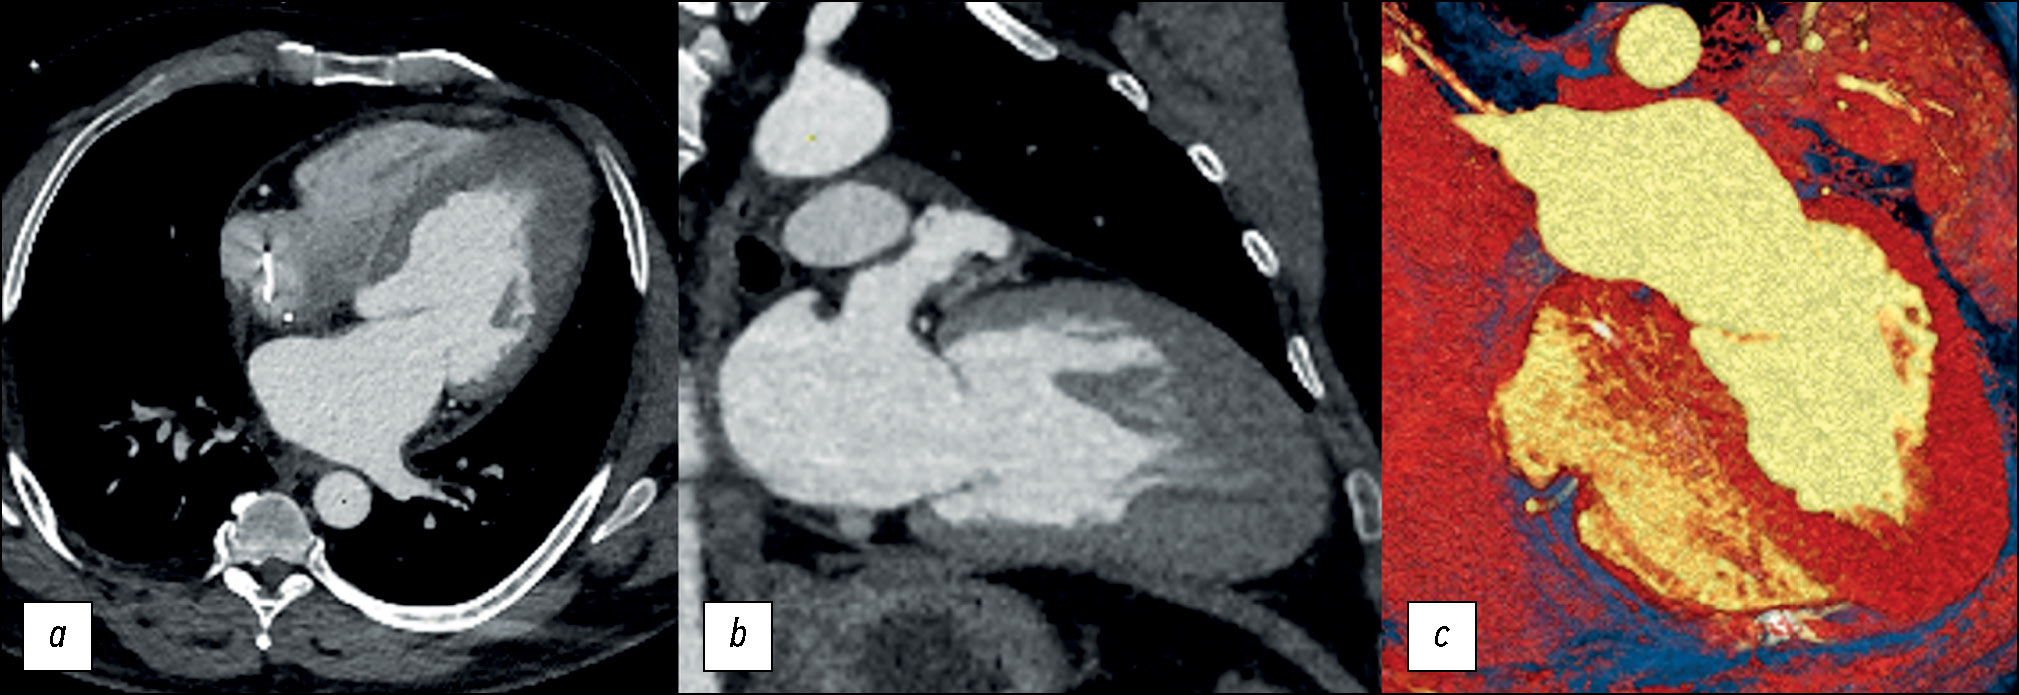

Протокол сканирования включал две фазы: ангиографическую и отсроченную. Первая, ангиографическая, фаза была выполнена согласно ранее апробированному протоколу на аппарате SOMATOM Definition Flash (Siemens Healthineers, Германия) (рис. 2).

Рис. 2. Пример пост-процессорной обработки изображений компьютерной ангиографии сердца пациента с гипертрофической кардиомиопатией. Визуализации полостей сердца, коронарных артерий и головок папиллярных мышц: a — 3D-реконструкция четырёхкамерной проекции сердца; b — 3D-реконструкция коронарных артерий; c — мультипланарная реконструкция в двухкамерной проекции сердца. ЛП — левое предсердие, ЛЖ — левый желудочек, ПП — правое предсердие, ПЖ — правый желудочек.